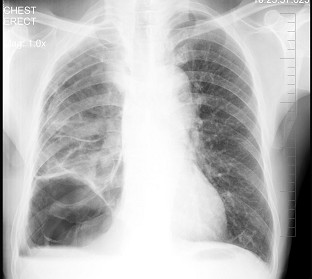

[单选题]男,62岁,常感胸闷、气逼,X线检查如图,最可能的诊断是()A.右侧肺大泡B.右侧气胸C.右侧肺脓肿D.右侧胸膜肥厚E.右侧肺气肿

[单选题]男性患者,62岁,常感胸闷、气逼,X线检查如图,最可能的诊断是()A .右侧肺大疱B .右侧气胸C .右侧肺脓肿D .右侧胸膜肥厚E .气胸